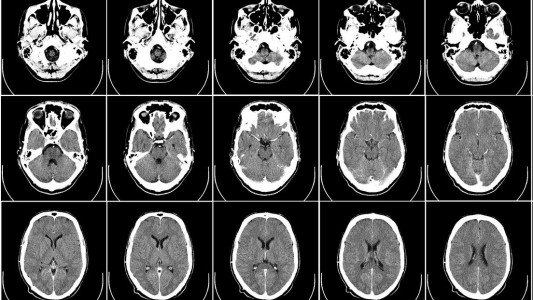

Era fanático de las plantas, estaba arreglando su jardín y una infección de la tierra le disolvió el cerebro